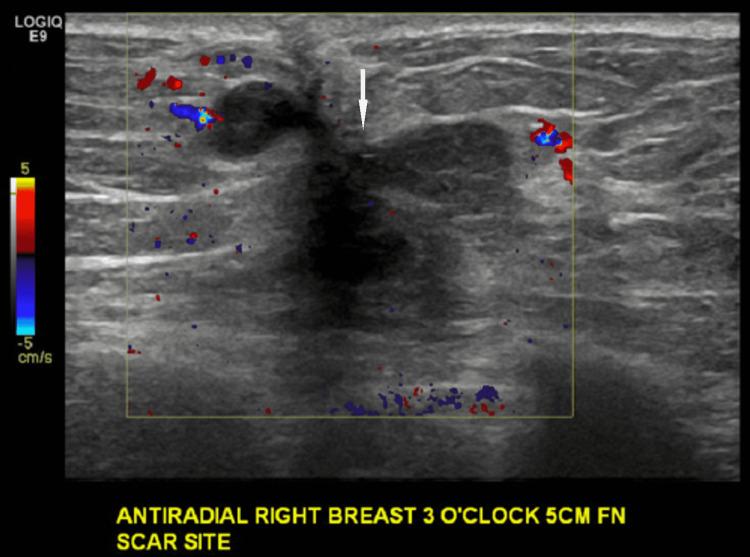

We describe a case of pathology-proven invasive lobular breast cancer (ILC) arising in a scar over 15 years after lumpectomy for previous invasive ductal carcinoma (IDC). The tumor was detected on screening mammography as a new focal asymmetry at the scar site and confirmed at diagnostic mammography. Ultrasound demonstrated an irregular, shadowing, hypoechoic mass at the scar site. Ultrasound-guided biopsy revealed poorly differentiated invasive lobular carcinoma. MRI and CT showed an irregular mass with pectoralis muscle invasion. Multimodality imaging findings are described. This is the first case to our knowledge reporting multimodality imaging findings of a breast cancer developing at the site of a surgical scar that is histologically different from the originally resected cancer.

我们描述了一例经病理证实的浸润性小叶乳腺癌(ILC)病例,该病例发生于先前因浸润性导管癌(IDC)行肿块切除术后15年以上的瘢痕处。肿瘤在筛查乳腺X线摄影中被检测为瘢痕部位新出现的局灶性不对称,并在诊断性乳腺X线摄影中得到证实。超声显示瘢痕部位有一个不规则、有阴影、低回声肿块。超声引导下活检显示为低分化浸润性小叶癌。MRI和CT显示有一个不规则肿块,侵犯胸大肌。描述了多模态成像结果。据我们所知,这是首例报告手术瘢痕部位发生的组织学上与最初切除的癌症不同的乳腺癌的多模态成像结果的病例。